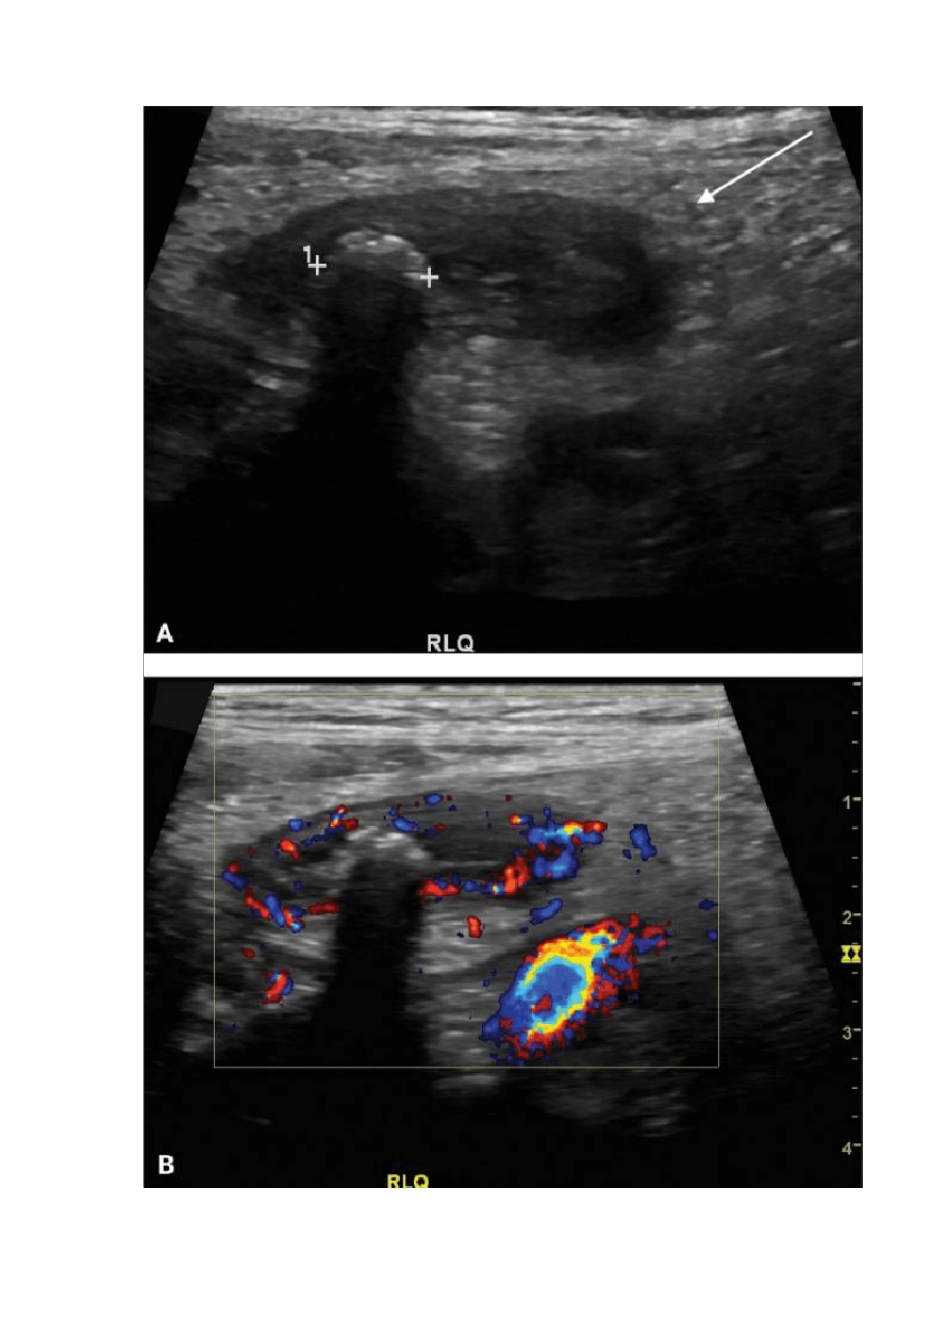

儿童腹痛超声诊断儿童腹痛很常见,但仅根据临床表现往往难以定性,常让临床医师头疼不已。超声对于鉴别急性阑尾炎、肠系膜淋巴结炎、胃肠炎、Meckel 憩室、肠套叠、卵巢扭转有其独到之处,且安全简便,日益受临床医师喜爱。急性阑尾炎急性阑尾炎是小儿腹部外科最常见疾病之一。正常阑尾为细长管状结构,一端连于盲肠,另一端为盲端,直径 ≤ 7 mm,探头挤压易压扁,且周围肠系膜无水肿(图 1)。彩色多普勒可辅助诊断急性阑尾炎,显示阑尾壁水肿充血(图 2)。阑尾周围炎是诊断阑尾炎可靠的间接征象。若阑尾周围脂肪回声均质、清晰,无继发炎症改变,则急性阑尾炎可能性不大(图 3)。阑尾穿孔的超声诊断敏感性为 86%,表现为粘膜下层回声局部中断,伴或不伴阑尾周围积液。若积液透声差或阑尾附近探及脓肿,则阑尾穿孔可能性大(图 4 和图 5)。阑尾穿孔破溃,有时不易发现异常阑尾,但见局限性脓液及粪石亦可考虑诊断。图 1 为正常阑尾声像图,其直径≦6 mm,起源于盲肠(箭头)图 2 为急性阑尾炎声像图:图 A 为阑尾肿大,其内见粪石伴声影(星号),周围肠系膜(箭头)呈炎性改变;图 B 为阑尾壁血流丰富图 3 为阑尾轻度肿大不伴阑尾周围炎:阑尾直径 6.5 mm,近端见粪石(箭头),周围肠系膜回声无改变,周围无积液;患者未予手术干预图 4 为伴有与不伴穿孔的两例急性阑尾炎:图 A 为阑尾黏膜下层(箭头)水肿增厚,阑尾未穿孔;图 B 为阑尾黏膜下层(箭头)中断,其周围呈「蜂窝状」回声改变,手术证实阑尾穿孔图 5 为阑尾穿孔:图 A 为肿大阑尾、粪石(箭头);图 B 为阑尾周围脓肿;图 C 和图 D 为 CT 冠状重建证实脓肿(图 C 箭头示肠石,图 D 箭头示脓肿)肠系膜淋巴结炎肠系膜淋巴结炎常继发于病毒性胃肠炎。肠系膜或右下腹淋巴结肿大常见于阑尾炎,若阑尾或其周围无炎症表现,则淋巴结肿大可考虑肠系膜淋巴结炎。目前并未有统一标准定义淋巴结肿大,部分学者以长径≧10 mm 作为标准,而有的则认为其短径超过 10 mm 才可。然而,淋巴结短径 ≤ 5 mm 也可出现临床症状。彩色多普勒超声可显示淋巴结内的血流信号,辅助诊断(图 6)。很多无症状儿童中,腹部也可发现稍肿大淋巴结,可能是处于淋巴结炎症早期,或为贾第鞭毛虫病、Crohn 病和 AIDS。若发现淋巴结相互融合、缺乏淋巴门或显著肿大,则应考虑到结核感染或淋巴瘤。若空肠近端、回肠末端肠壁增厚,则可考虑肠炎。图 6...